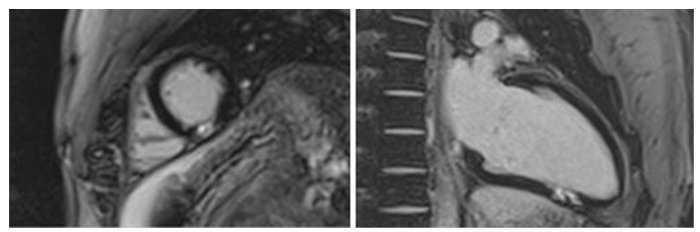

Davant la troballa de l’extrasistòlia ventricular en la prova d’esforç es sol·licita ECG de senyal mitjana: normal. Holter cardíac: ritme sinusal. FC mitjana: 66 bpm, 2 extrasístoles ventriculars en 24 h. Tomografia coronària: artèries epicàrdiques sense lesions coronàries i ressonància cardíaca amb adenosina: absència d’isquèmia induïble, FEVE 60%, àrea focal de contrast tardà transmural en el segment mitjà inferior del ventricle esquerre (fig. 3).

Figura 3. Ressonància cardíaca, contrast tardà transmural.